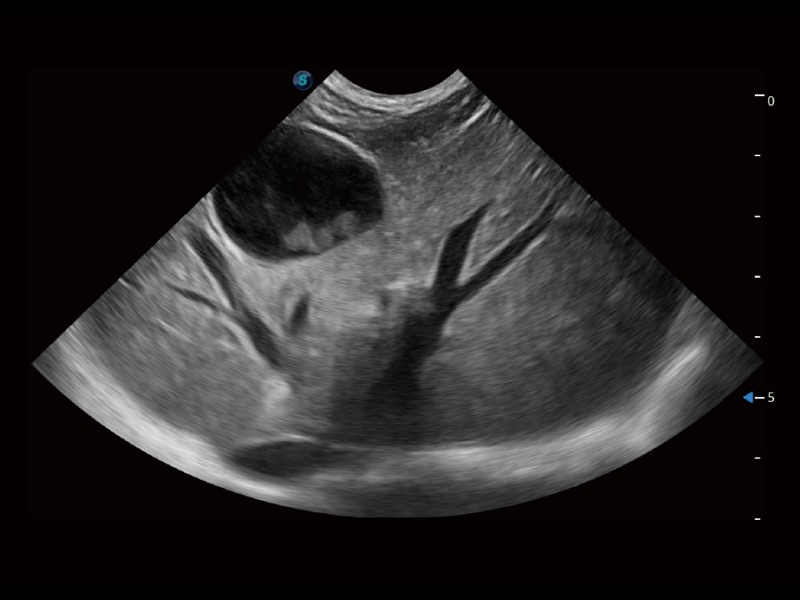

动物是人类最亲密的朋友和最值得信赖的伙伴。环球UG官网也一直致力于探索动物专用的超声影像解决方案。全新推出的ProPet系列,是环球UG官网在动物超声影像智能化、专业化、精准化的一次跨越式革新。动物不能用言语来表述自己的不适,通过超声影像,ProPet系列搭建了动物医生与不同物种沟通的“桥梁”,为动物医生注入了“治愈之力”。 ProPet 70将是您值得信赖的超声伙伴。它配备了复合材料线阵探头,帮助动物医生获得卓越精准的临床图像。同时ProPet 70直观便捷的操作体验以及专业的测量工具,可为不同体型和生理结构的动物带来全面临床评估,切实为动物医生提供智能、专业、精准的超声影像解决方案。

ProPet 70 进一步提升了微米成像算法,更加注重对基础原始图像的还原和保留,在有效减少斑点噪声、增强组织边界显示的同时,避免过度优化丟失真实的解剖信息。

ProPet 70专为动物医生设计,对不同的动物体型和生理结构作出了针对性的优化。通过动物影像专用软件,可满足个性化的应用需求,帮助动物医生获得更精确的诊断数据。

ProPet 70 全新的动物超声智能软件和丰富的探头群,为动物医生提供了高清晰度和精细分辨率的图像,无论在宠物、马科、畜牧还是实验室动物等应用中都可以轻松应对,为您的日常工作带来满意的体验。